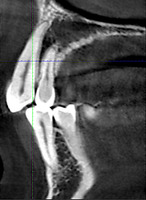

При анализе и описании компьютерной конусно-лучевой томографии (рис. 2а-г) была выявлена генерализованная первичная дегисценция вестибулярной пластинки кости от 1/2 до 3/4 длины корней зубов, зубной ряд целостный, все зубы витальны, кариозных поражений нет. Тип кости 1-2 (Lechkolm и Zarb, 1983), первичная дегисценция вестибулярной костной пластинки превышает пределы возрастной атрофии.

Через 12 месяцев (рис. 7а-г) на срезах компьютерной томограммы 11-ый и 13-ый зубы находятся в костной ткани, при этом костные пики и перегородки укрепились, объем их увеличился; вестибулярно заметен объем костной массы, предположительно компактной формации, исходя из электронной плотности участка. Этим объясняется отсутствие рецидива при лечении рецессии десны как в случае применения аутотрансплантата, также и ТМО (dura mater).